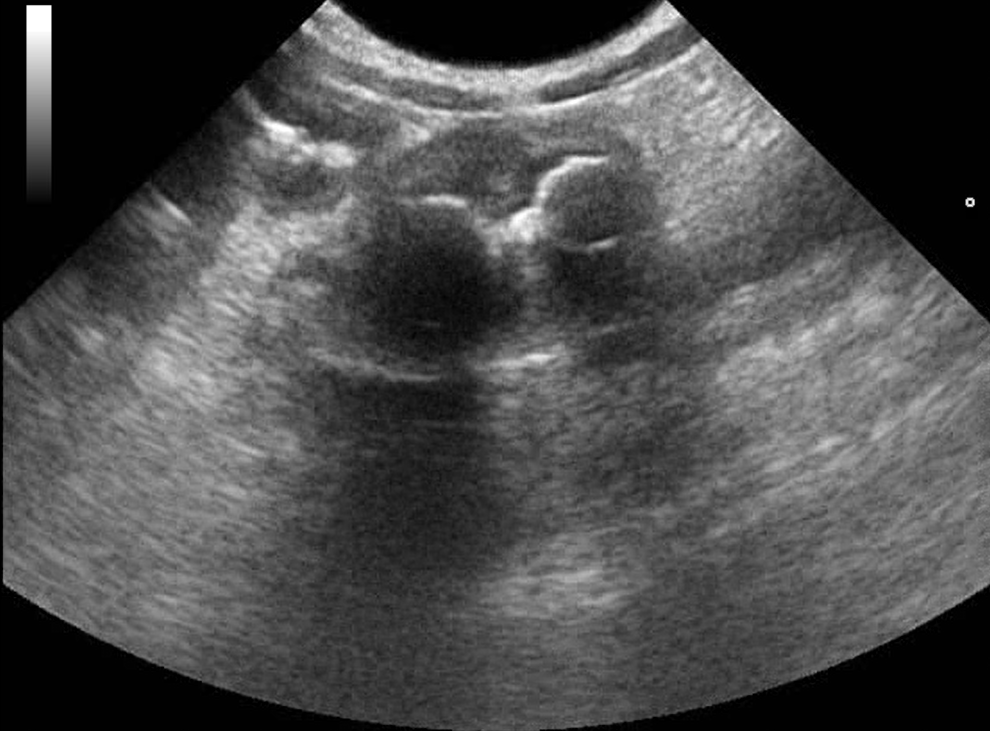

Webinář zaměřen na klinicky orientovanou sonografii gastrointestinálního traktu, se zaměřením na patologické nálezy, které mají přímý dopad na další diagnostický a terapeutický postup. Čeká na vás více než 50 komentovaných videosmyček z reálných klinických případů.